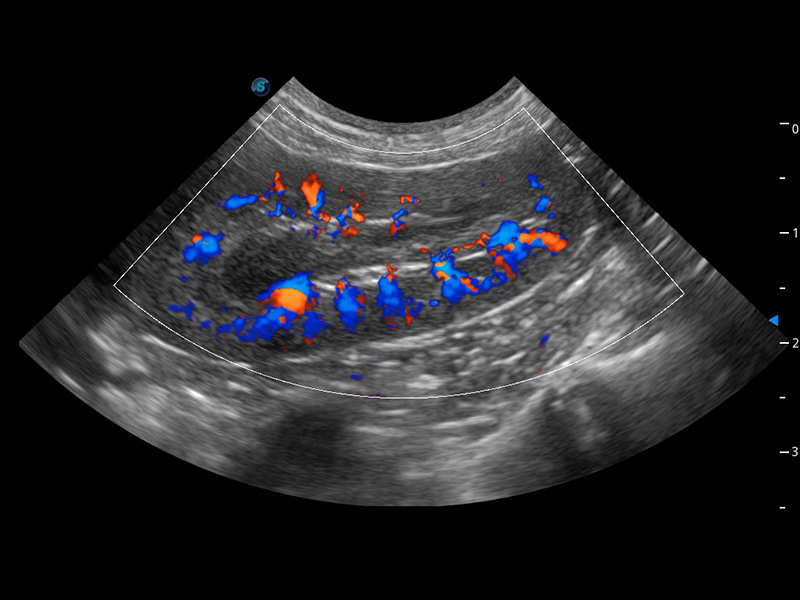

ProPet 60 作为一款高端台式动物超声设备,为动物医生的日常诊断提供了一系列贴合动物临床需求、解决临床实际问题的高级成像功能。凭借全系列高清探头,满足医生对腹部、心脏、生殖、浅表、肌骨等成像的所有需求,切实帮助您提升检查效率,提高诊断信心。

动物是人类最亲密的朋友和最值得信赖的伙伴。环球UG官网也一直致力于探索动物专用的超声影像解决方案。 全新推出的ProPet系列,是环球UG官网在动物超声影像智能化、专业化、精准化的一次跨越式革新。动物不能用言语来表述自己的不适,通过超声影像,ProPet系列搭建了动物医生与不同物种沟通的“桥梁”,为动物医生注入了“治愈之力”。